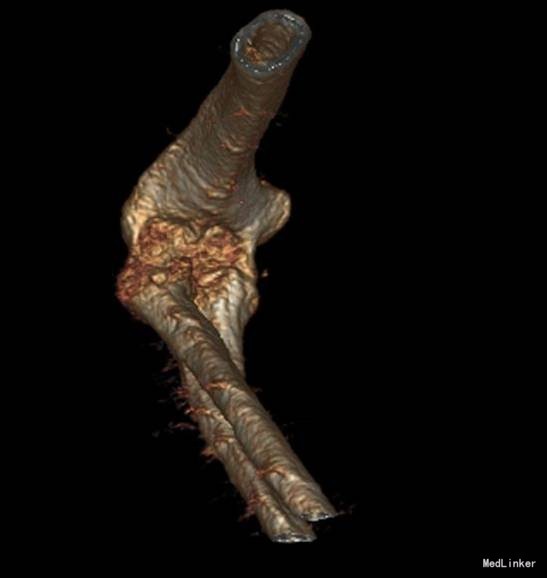

主诉:摔伤后右肘部疼痛10小时 患者自述2014-9-2 早8点自己走路时不小心摔倒,右肘部着地,导致右肘部疼痛、肿胀、活动受限,于当地医院拍片诊断为“右肘关节脱位”,给予手法复位, 为求进一步治疗来我院,诊断为“左肘关节骨折”,并收入我科,患者自受伤以来,无发热,无呼吸困难,无腹痛腹泻,饮食睡眠正常,大小便未见异常。

患者步入病房,左肘关节肿胀明显,压痛(+),骨擦音及骨擦感(+),左上肢感觉未见异常,左手指活动正常,左桡动脉搏动可触及。

患者入院后左肘关节石膏固定,左肘关节对症消肿等治疗。1周后完善检查后查无明显手术禁忌症后行左桡骨小头骨折切开复位内固定术。